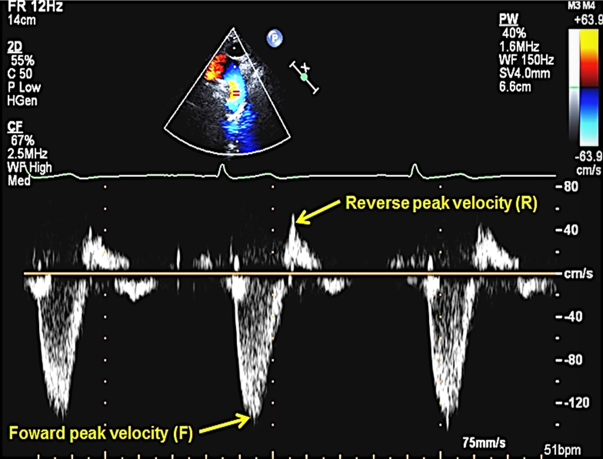

how is descending ao diastolic flow assesed?

taken at subcostal and SSN

look for evidence of holodiastolic flow reversal ( should not see SUSTAINED flow reversal thorugh diastole in aorta → severe regurg)